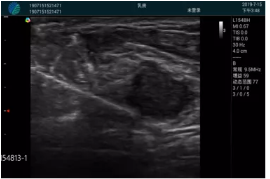

清晰顯示腺體內(nèi)低回聲快影,邊界清晰,包膜較光滑

確定進針路徑并實時監(jiān)測抽吸針與腫塊位置關系

抽吸針進入腫塊內(nèi)部進行旋切

抽吸過程中可見腫塊明顯縮小,并根據(jù)腫塊位置改變針道位置

抽吸旋切后再進行超聲復查,原腫塊區(qū)域未見殘留組織及出血